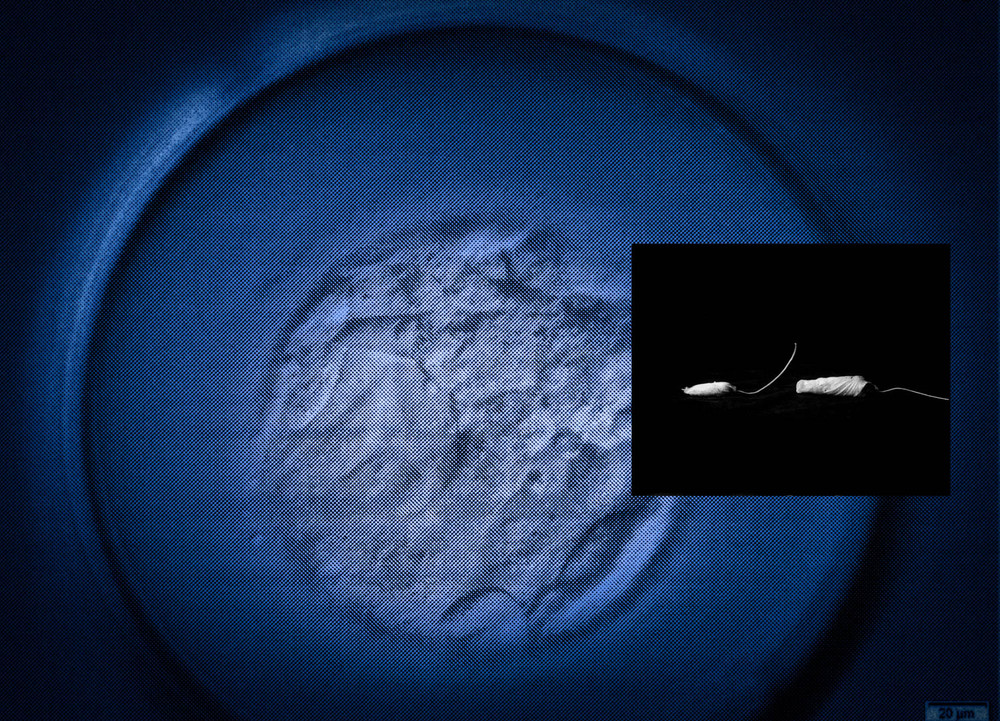

After treatment, the clinic gave Suzuki four scans depicting her fertilized eggs. Suzuki combined these with an image of a hibiscus bud, which she found on the street. “The flower had fallen before blossoming,” she remembers. “In that moment, I saw the life of a woman who could not fulfill her role.” The artist attached a thin string to the flower to resemble a tampon, and collaged it with her scans. “In the final piece, it looks like a sperm heading toward the egg.”